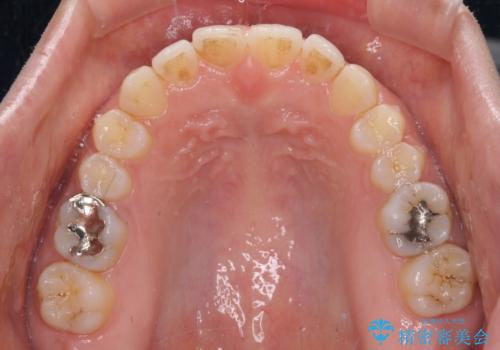

受け口傾向の前歯 すきっ歯の改善

舌癖を改善したことで、隙間や突出感を改善することができました。

隙間は後戻りしやすいため、舌側を細いワイヤーで固定することとしました。